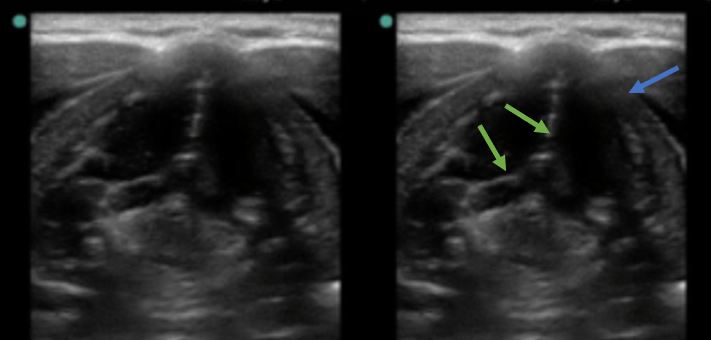

En la figura 3 se aprecia el corte transversal del cuello a la altura del cartílago tiroides. Observamos la estructura hipoecogénica del cartílago tiroides (flecha azul). En este caso, vemos la glotis cerrada (cuerdas vocales aproximadas, flechas verdes).